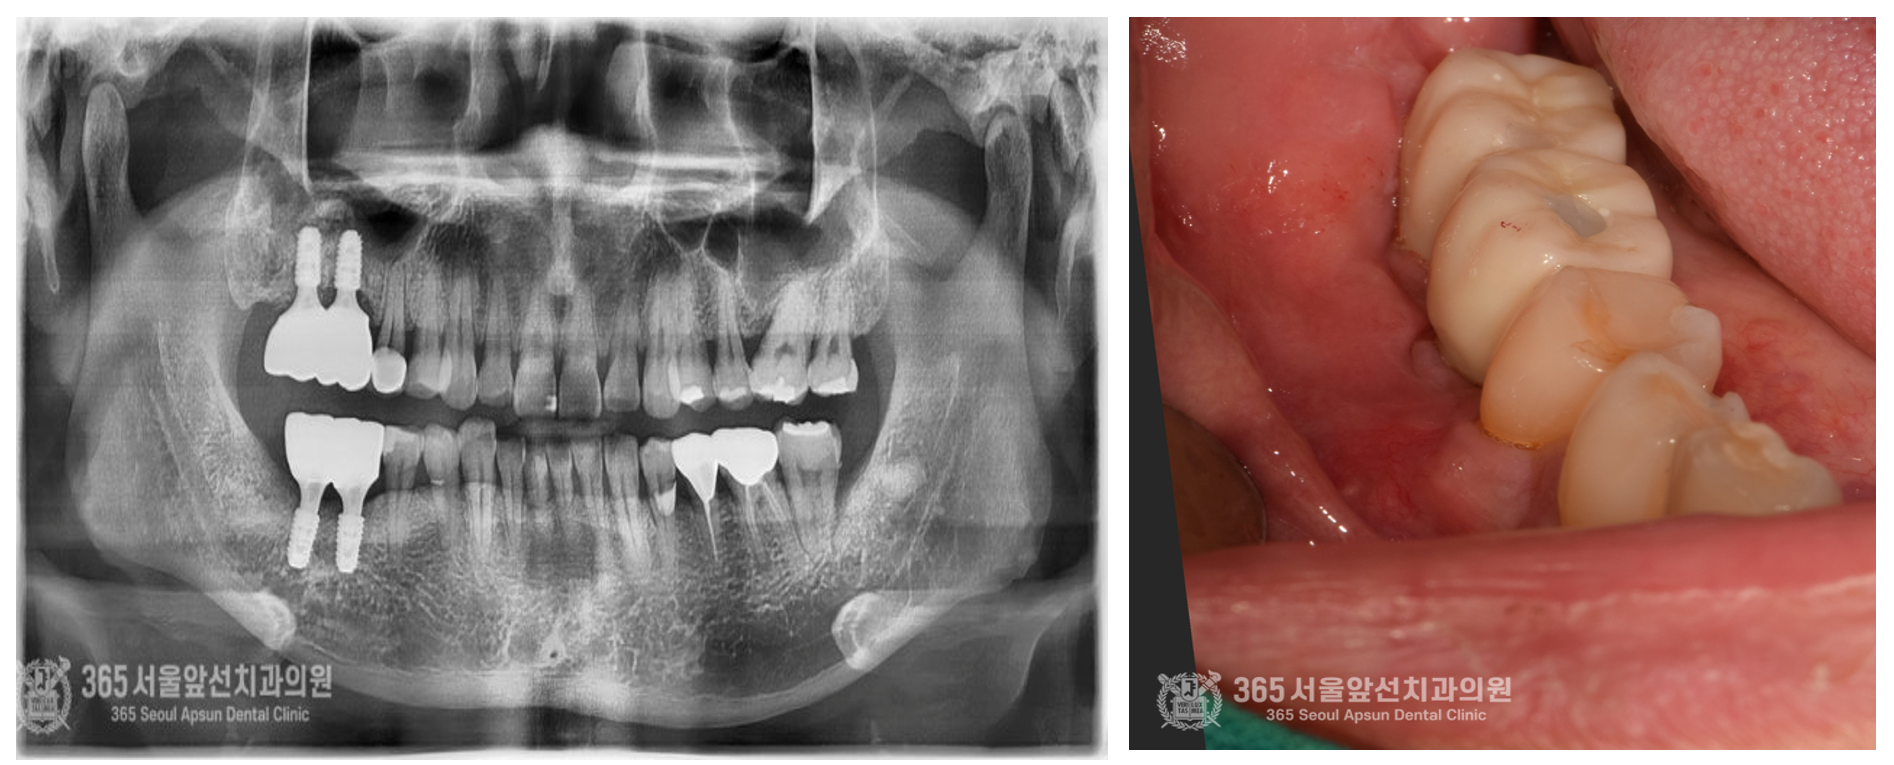

촬영일자:24.05.09 처음 내원 당시 엑스레이 사진입니다. 사진상에서 왼쪽편에 매복된 치아들이 관찰되며, 신경관에 치아뿌리가 닿아 있어서 난이도가 높은 발치로 예상됩니다. 잇몸과 치아의 다양한 문제점들이 섞여있던 상황으로 매우 복잡한 상황입니다.

촬영일자:24.05.09 발치 후 체크약속때 엑스레이 사진입니다. 해당측의 치아들은 이미 잇몸뼈의 소실이 너무 심각하여 사용할 수 없는 수준이었기에 신경이 손상되지 않도록 조심스럽게 발치를 진행하였습니다.

촬영일자:25.01.15 좌측 이미지는 치료 종결 후 엑스레이 사진입니다. 난이도 높은 매복치 발치와 뼈이식, 임플란트 식립 및 보철까지 정확하게 이루어진 것을 볼 수 있습니다. 또한 우측 이미지는 보철물이 들어간 후 촬영한 구강내 사진입니다. 치아색이 나는 보철물을 만들어어드렸고 매우 자연스러워 보입니다. 오늘은 매우 난이도가 높았던 치료 증례를 소개해드렸는데요. 앞으로도 도움이 되는 포스팅으로 찾아뵙겠습니다. 지금까지 난이도 높은 치료일수록 더 자신있는 도화역치과 365서울앞선치과 강동우 대표원장이었습니다! 감사합니다. [치료기간:2024년 5월9일 ~2025년 1월 15일] ※365서울앞선치과의원의 모든 포스팅은 각 진료과 의료진이 직접 작성합니다. 365서울앞선치과의원 블로그의 임상 케이스 게시물은 환자분께 의학적으로 정확하고 상세한 정보를 드리기 위해 각 진료과 의료진이 직접 작성하며, 모든 증례 사진은 본원 의료진이 직접 시술한 증례를 촬영한 것으로, 의료법 제23조, 제56조에 의거하며 환자분의 동의를 얻어 포스팅에 사용하였습니다. 또한 해당 케이스는 본 환자분의 치료 결과이며, 환자 상태에 따라 치료의 결과는 달라질 수 있습니다. |